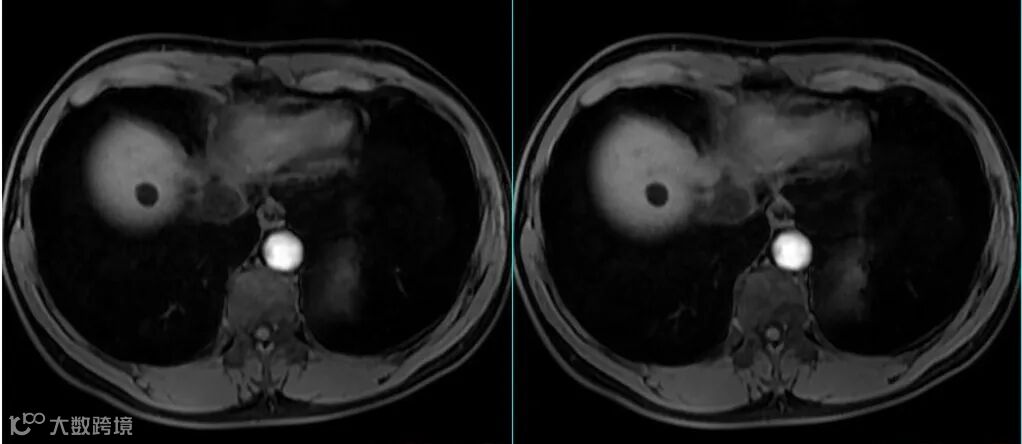

MRI图像上的组织信号与诸多因素相关,如序列、参数、组织本身的状态等。所以应首先要看是什么序列,使用的什么参数,目标组织的状态是怎样的。 -

MRI上的信号是相对的,没有绝对的高与低,而要看与谁比,在解读MRI图像信号时要选取信号相对稳定的组织作为参照对比,如肌腱,脑脊液。 -

在增强机理方面,MRI“对比剂”与CT“造影剂”有着本质的区别。钆对比剂本身并不会产生信号,而是当钆对比剂与水分子的距离足够近时,通过缩短周围水质子的T1弛豫时间来间接产生“增强”的作用。切记不要以信号强度的高低来判定摄取对比剂浓度的多少。